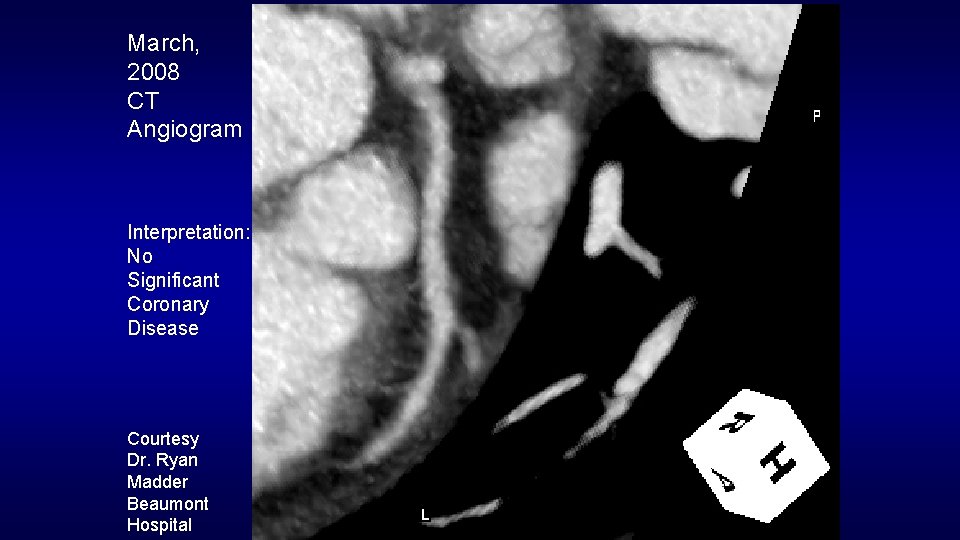

March, 2008 CT Angiogram Interpretation: No Significant Coronary Disease Courtesy Dr. Ryan Madder Beaumont Hospital